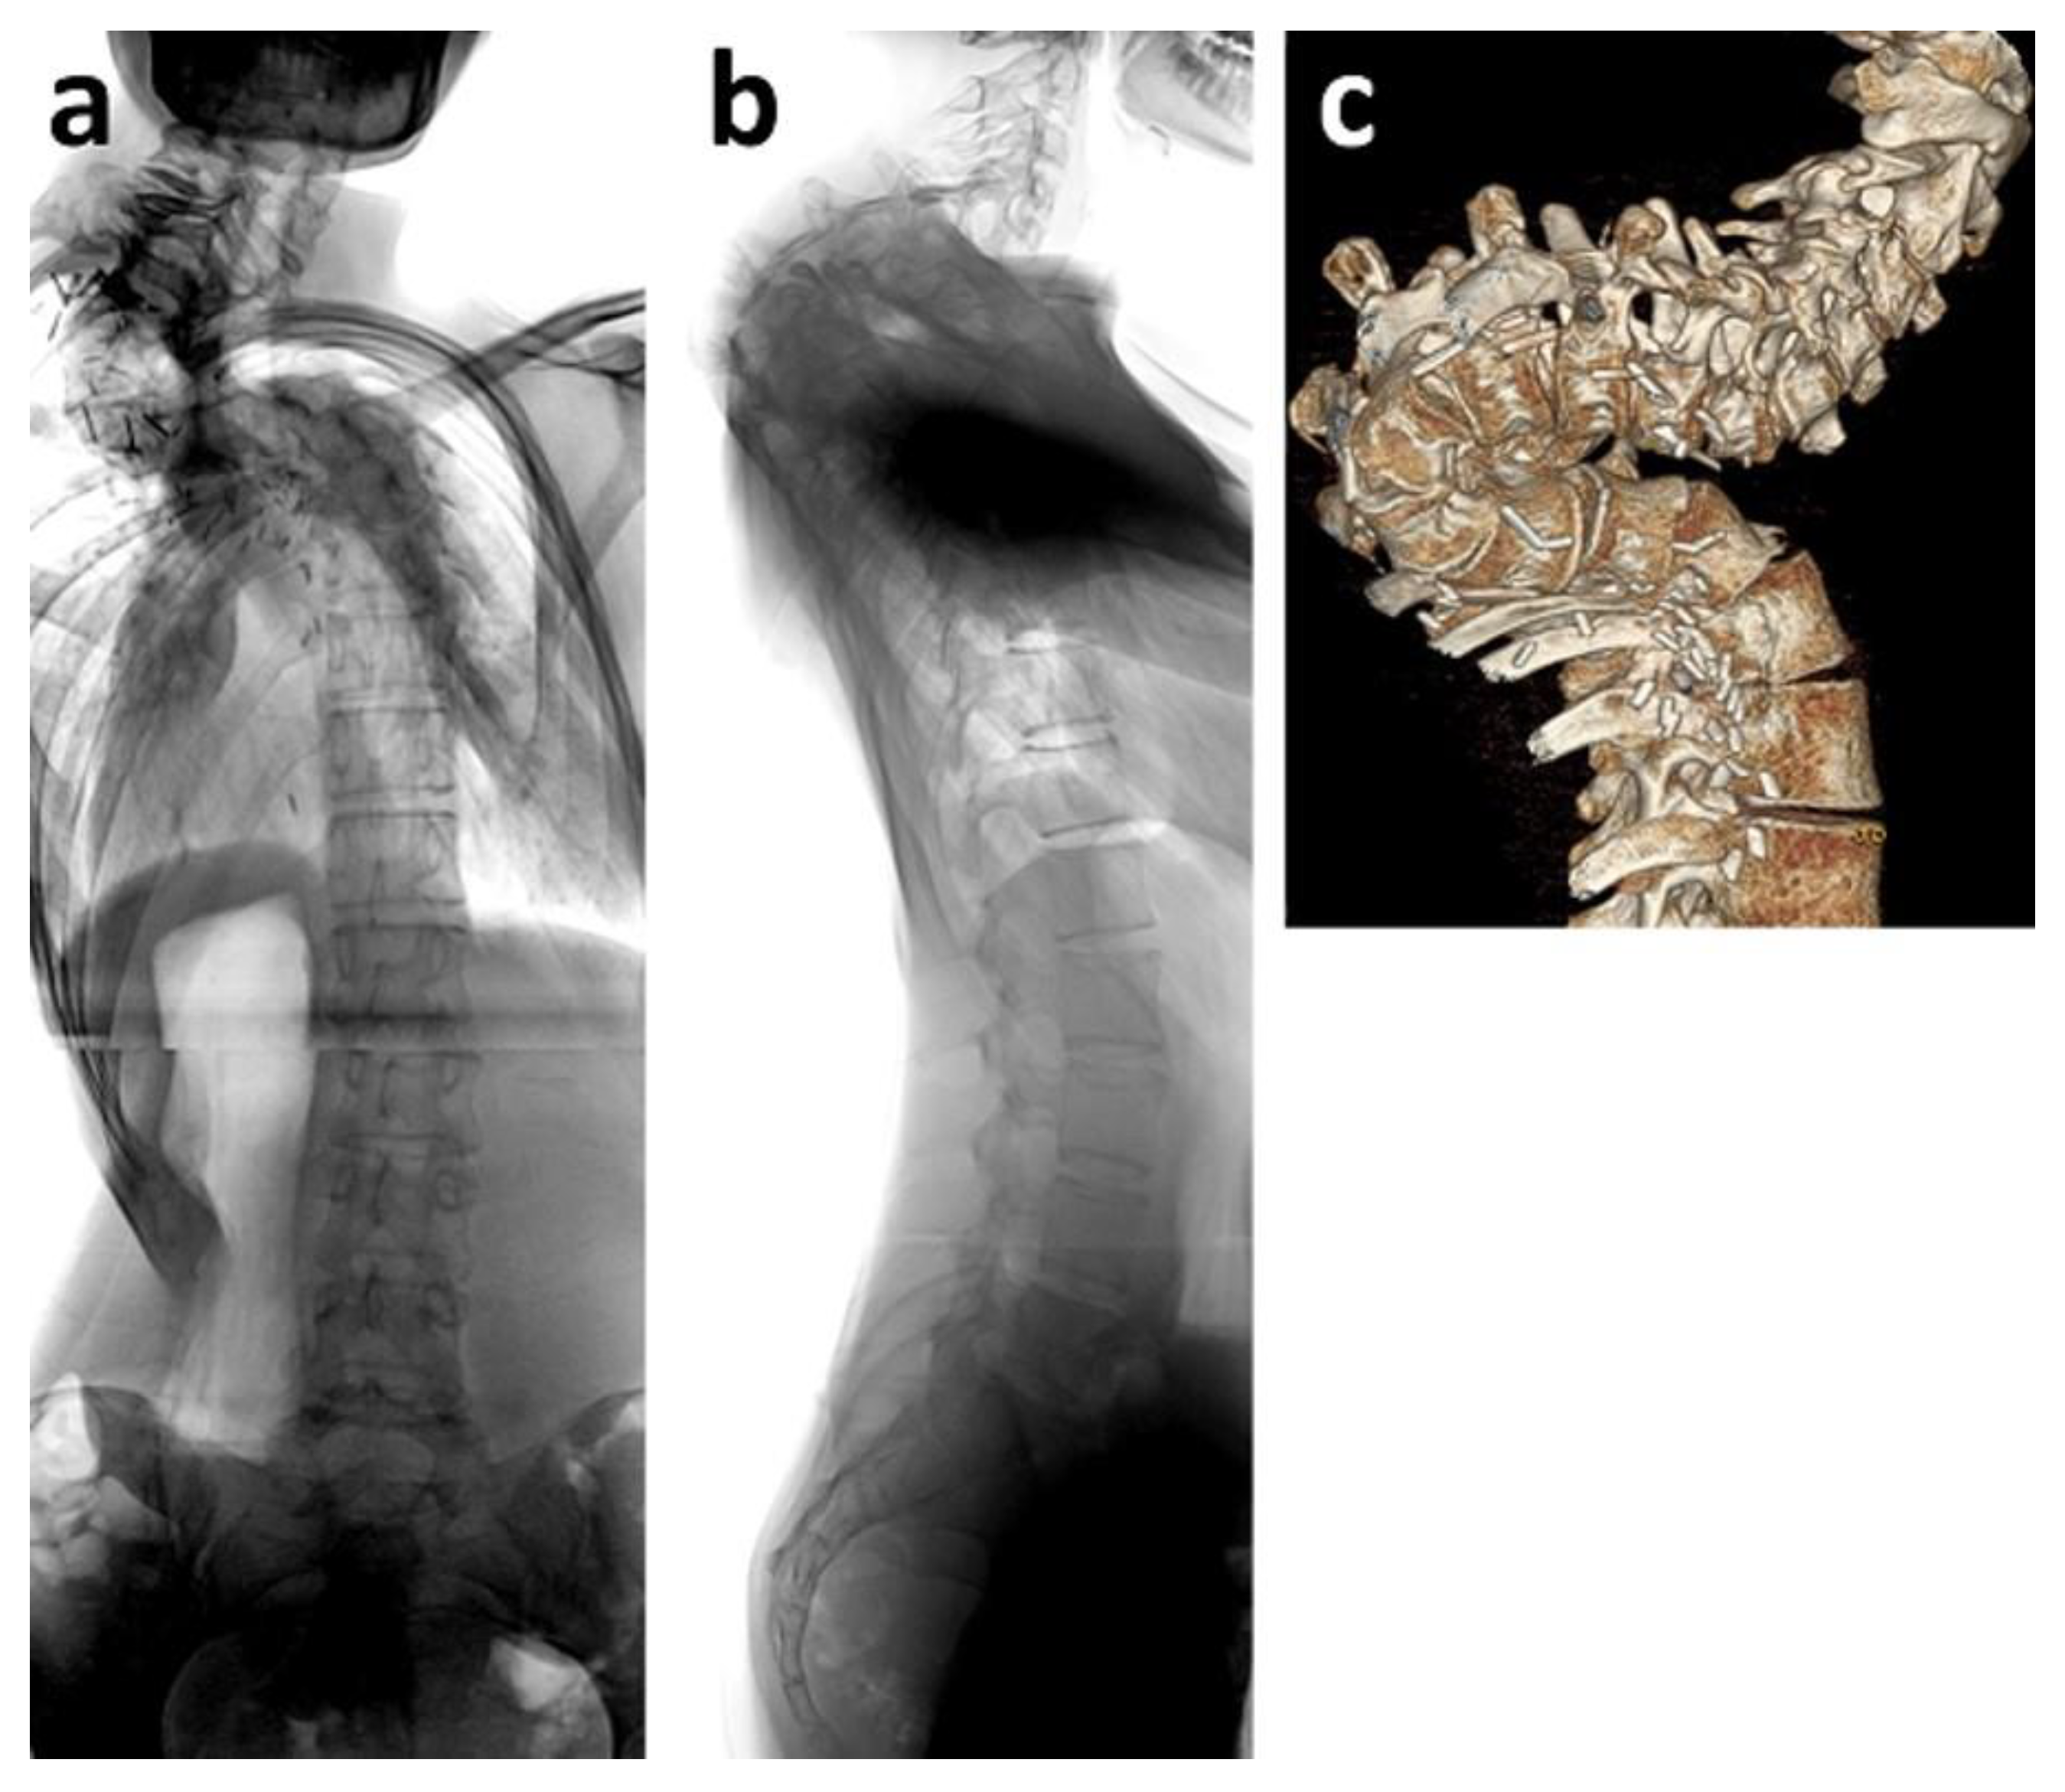

Figure 3. Fifteen-year old boy who was diagnosed with intraspinal astrocytoma at age ten. He received chemotherapy and radiotherapy. Five years later, severe thoracic spinal deformity had developed (ac). Halo traction was applied for gradual scoliosis and kyphosis correction as well as reduction of the surgical risk due to neurological deterioration (d,e). Surgery was performed using spinal cord monitoring. When erecting the spine, motor evoked potentials (MEP) disappeared. After controlling correct screw placement by computed tomography, spinal deformity correction could only be performed until MEP weakened, thus leaving considerate kyphosis as a residual deformity (f,g).

During puberty, twelve patients with spinal deformities received a definite spinal fusion. Reasons were scoliosis alone (n = 2), kyphosis alone (n = 2), or a three-dimensional deformity (n = 8). In two cases with severe, high, and rigid thoracic deformities of 108° and 105° (Figure 3), halo traction was applied for eight weeks prior to surgical intervention, in order to reduce the deformity through gradual correction. No neurological impairment occurred during halo traction. Despite thorough pre-surgical and intra-surgical planning and spinal cord monitoring, loss of motor function potential did occur in these severe cases during surgery. After ruling out screw misplacement by CT scans, deformity correction was reduced to a point of compromise between the best possible alignment and full motor function potential (Figure 3).